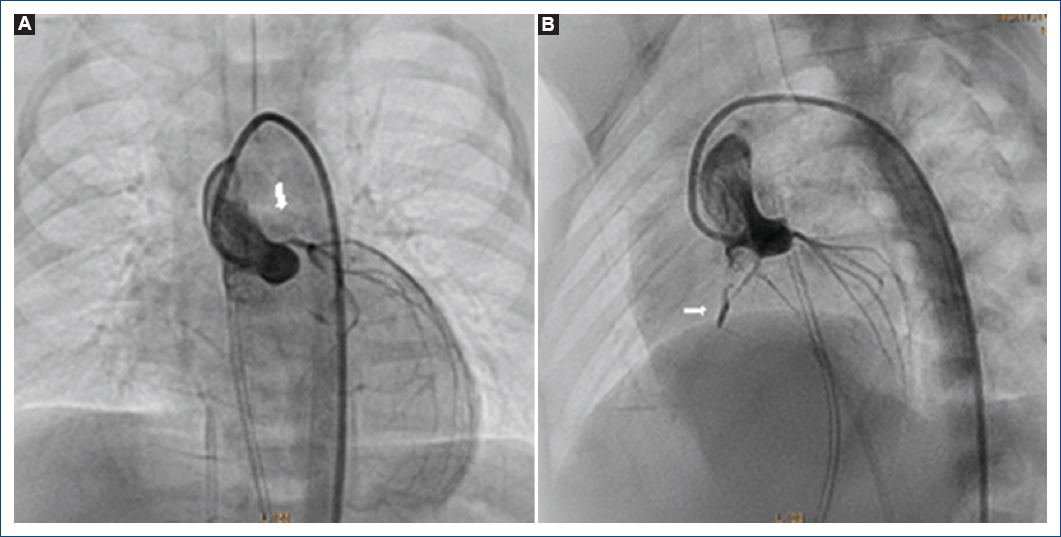

El gran reto de esta patología es la variabilidad interoperador que existe en la interpretación de los estudios angiográficos, incluso se ha desarrollado una escala o score basado en un puntaje tratando de detectar a los pacientes con CCVDD6. En Japón se reportó una descompresión transitoria transquirúrgica por Iwai et al.7, confirmando la CCVDD en un paciente previo a la derivación cavo-pulmonar. Lo anterior hace difícil establecer la mejor conducta terapéutica para cada paciente, por lo que pensamos que con el método angiográfico se está sobreestimando a muchos pacientes con CVC y muchos de estos realmente no tienen CCVDD, en contraparte algunos pacientes sin atresia de los ostium coronarios pueden ser realmente CCVDD (como los tres casos presentados), pero existe el riesgo de que cuando se les ofrece descompresión del VD, es entonces cuando el equipo cardiovascular se percata de la CCVDD, como han reportado otros autores, que presentan este tipo de errores de interpretación del estudio angiográfico2, por tal motivo en el Departamento de Hemodinámica del Instituto Nacional de Pediatría de México se diseñó una maniobra de descompresión transitoria percutánea que podría evaluar de forma objetiva aquellos casos donde exista duda de la existencia de la CCVDD (Fig. 11). Maniobra de descompresión transitoria.

Figura 11 Maniobra de descompresión transitoria del ventrículo derecho. A: previo a la descompresión. B: descompresión del ventrículo derecho, la segunda llave se gira 90° en sentido horario, se permite el flujo libre del ventrículo derecho hasta la vena cava inferior con registro simultáneo de presiones.

La técnica o maniobra propuesta consiste en introducir un catéter multipropósito (diagnóstico) o un catéter guía Judkins derecho en la cavidad ventricular derecha sobre una guía de angioplastia coronaria 0.014”, este catéter se conectará en su parte distal a un circuito de puertos o llaves. como por ejemplo un manifold de tres puertos (válvulas o vías), en donde el primer puerto o vía (proximal) se conectará a un registro de presiones invasivas y el segundo puerto se conectará a la vía lateral de introductor arterial colocado en la vena femoral (se recomienda al menos 2 Fr mayor al tamaño del catéter utilizado), siendo el objetivo producir insuficiencia tricuspídea que mimetice una descompresión transitoria del VD, la tercera vía podrá utilizarse para administrar medio de contraste o puede permanecer cerrado. De manera inicial se realizará registro de presiones comparando la presión del VD y del VI o la aorta (Ao), manteniendo el segundo puerto cerrado (Fig. 11A), posteriormente se abrirá este segundo puerto (Fig. 11B) para que el flujo del VD fluya por el catéter-circuito de llaves o puertos y finalmente llegar libremente a la vena cava inferior. Se registrarán las curvas de presión de forma simultánea (VD y VI o Ao) y se realizará monitoreo hemodinámico, además de registro de EKG. La prueba o maniobra de descompresión transitoria se interpretará como negativa si no hay descompensación hemodinámica, ni datos de isquemia, lesión o infarto. En contraparte, será positiva si el paciente presenta deterioro hemodinámico con hipotensión, bradicardia, isquemia, lesión o infarto.

La maniobra será muy útil para el pronóstico de los pacientes con «verdadera» CCVDD, ya que la mejor conducta en esta situación sería referir tempranamente a estos pacientes a un centro con trasplante cardiaco, o en su defecto, en caso de no ser posible el trasplante, informar del mal pronóstico para la vida a los familiares a corto, mediano o largo plazo y evitar realizar procedimientos quirúrgicos o intervencionistas (p. ej., septostomía atrial) que no tendrán ningún beneficio para el paciente o que incluso pudieran ser deletéreos para la fisiología de los pacientes con CCVDD.